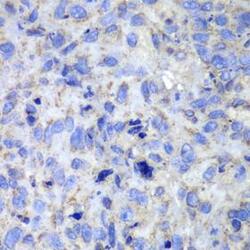

- Immunohistochemistry of paraffin-embedded human lung cancer using CASP7 antibodyat dilution of 1:100 (40x lens).

Explore